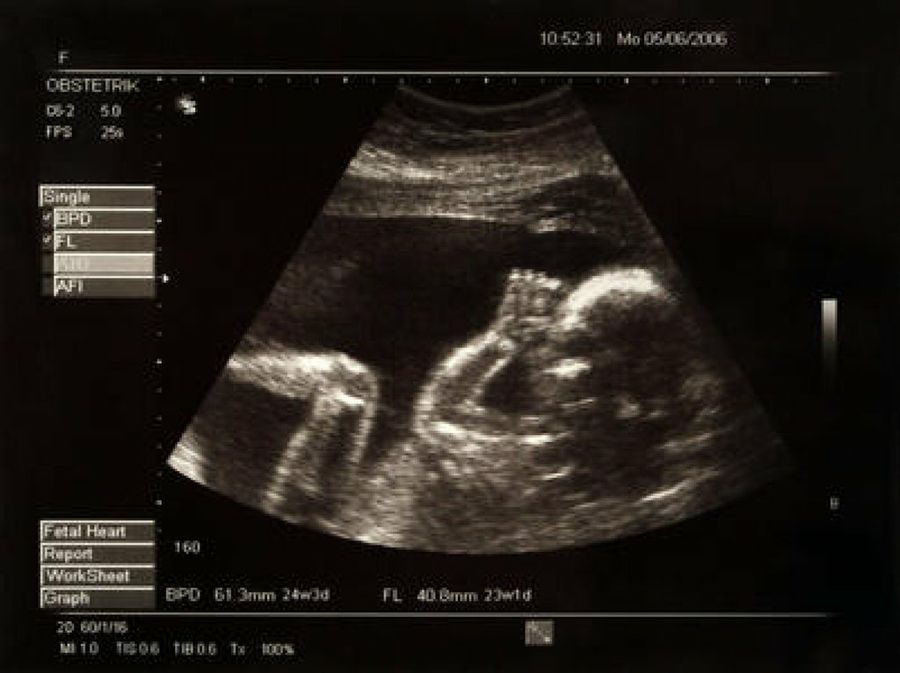

ecografía bebe

En el último mes de la segunda etapa del embarazo nuestro bebé llega a los 640 grs. y mide unos 30 cm. Se le marcan las líneas de las manos y los pies, se enrojece la piel y los párpados se empiezan a despegar, consiguiendo que nuestro bebé abra los ojos por primera vez. Todavía los pulmones no son lo demasiado grandes como para respirar fuera de su madre, aunque sí podría sobrevivir con cuidados intensivos en el caso de que se adelante prematuramente el parto